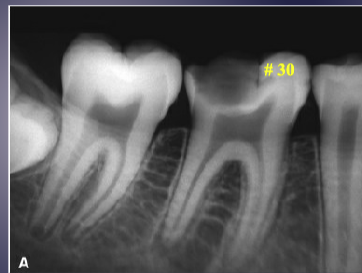

differentiate the pathology for #30 + #31

#30: apical rarefying osteitis

#31: developing tooth w/ open root apex

what’s the pathology of #7

apical rarefying osteitis

what’s the pathology of #30

apical sclerosing osteitis

describe the pathology

apical sclerosing osteitis + radiolucency around PDL space